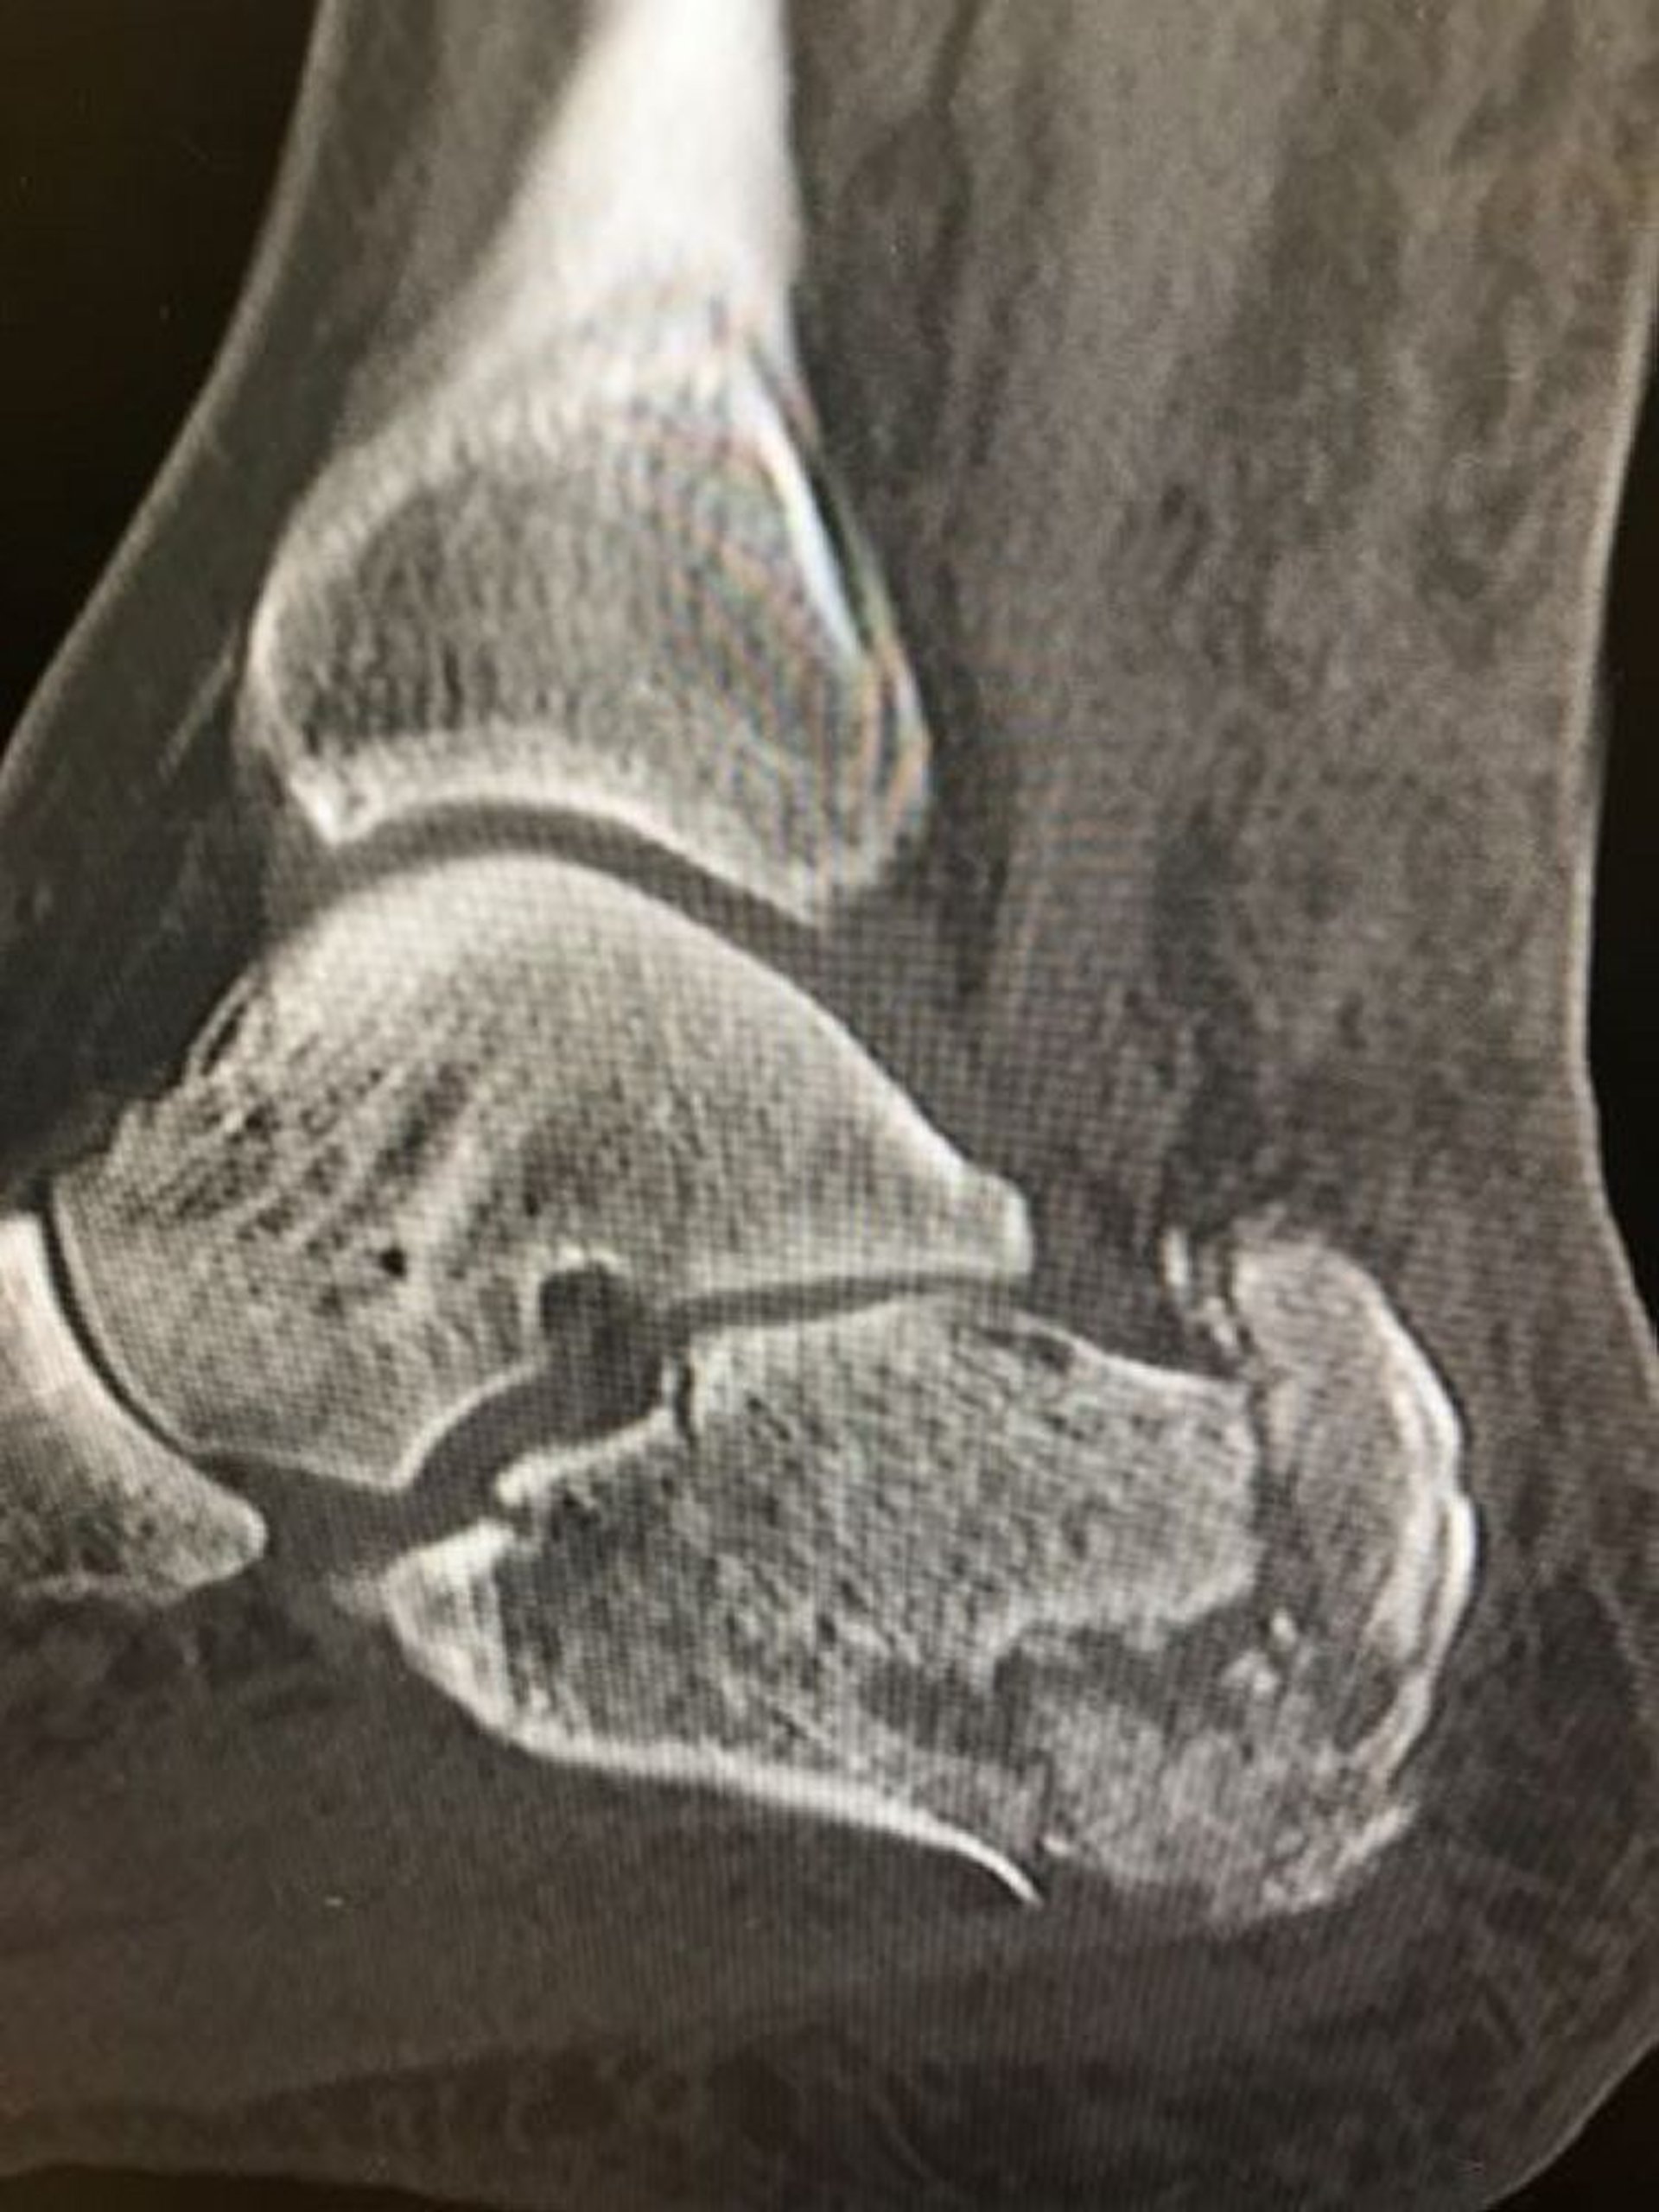

Diese Röntgenaufnahme zeigt eine Trümmerfraktur des Kalkaneus.

Image courtesy of Danielle Campagne, MD.